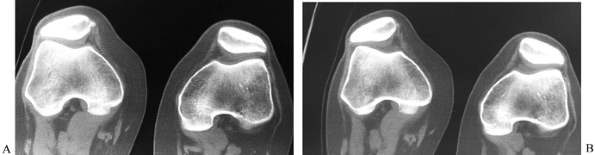

has declined with the advent of MRI, but it remains useful in the

diagnosis of osteonecrosis, OCD, tibial plateau fractures, and tumors,

as well as for evaluation of patellar tracking, patellar tilt, and

patellar subluxation (Fig. 84.20).

Figure 84.20. CT image of the patellofemoral joint at 30° (A) with quad tightening and (B) without quad tightening.